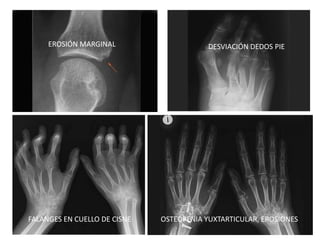

EROSIÓN MARGINAL DESVIACIÓN DEDOS PIE

FALANGES EN CUELLO DE CISNE OSTEOPENIA YUXTARTICULAR, EROSIONES

Apoyan al Dx clínico. Ningún hallazgo es dx en sí.

1. Tumefacción de partes blandas (lo más precoz).

2. Osteopenia yuxta-articular.

3. EROSIONES ÓSEAS:

- Mal pronóstico si precoces.

- En forma de quistes subcondrales o pérdida de

cartílago.

4. Luxaciones/subluxaciones.

5. LA RX PUEDE SER NORMAL

6. La RMN de manos ofrece mayor sensibilidad que la Rx

HALLAZGOS RADIOLÓGICOS